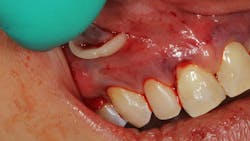

Gingival recession, more commonly described as the condition where the gum tissue surrounding the teeth pulls back, leading to root exposure, is a common periodontal concern (figure 1). Addressing this issue is not only crucial for maintaining oral health but also for achieving cosmetic satisfaction, particularly in individuals dealing with multiple teeth affected by recession (MAR).

PST, developed as a minimally invasive procedure, is designed to reposition gingival tissue to cover exposed roots.1,2 Unlike conventional methods, PST eliminates the need for grafting with tissue from the palate and invasive incisions, significantly reducing postoperative discomfort and scarring (figure 2).